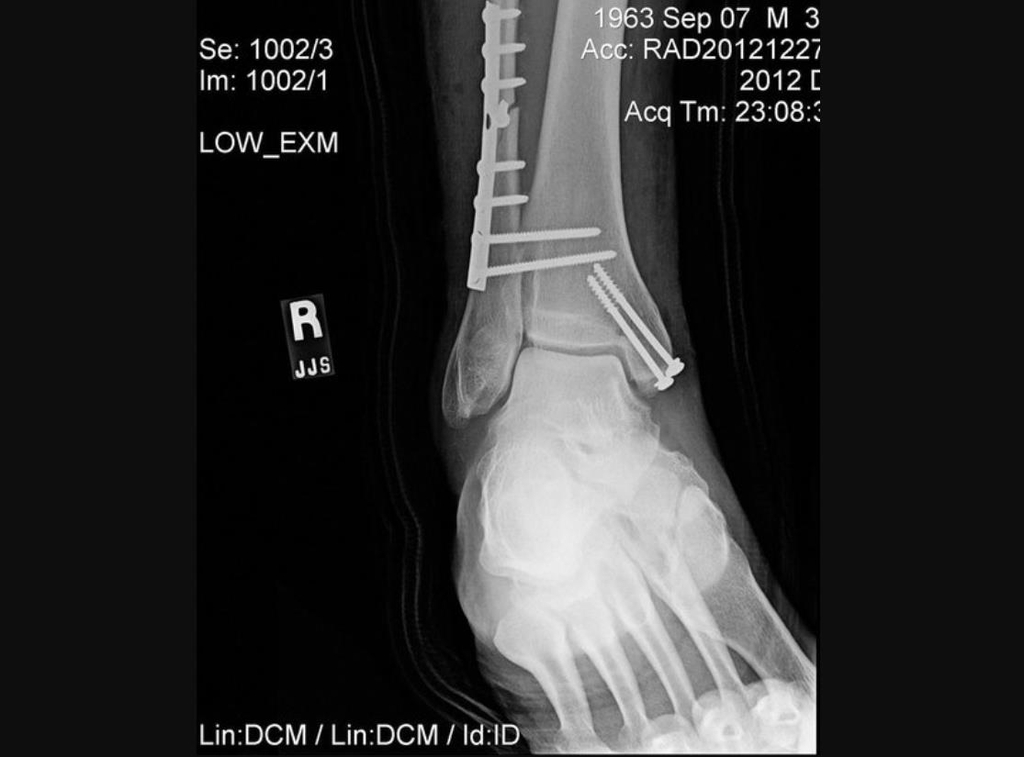

이 사고로 그는 오른쪽 다리뼈 여러 군데가 산산조각이 나면서 부러진 뼈가 피부를 찢고 돌출되는 '분쇄 개방 골절'을 입었으며, 철심을 박아 정강이뼈와 종아리뼈를 고정하고 발과 발목뼈는 수술용 나사와 핀으로 안정시키는 수술을 받았다.

의료진은 철심을 박아 무릎 아래 두 개의 긴 뼈인 정강이뼈와 종아리뼈를 고정했다.

또 발과 발목뼈는 수술용 나사와 핀으로 안정시켰다.

수술용 나사와 핀으로 뼈를 고정한 모습: [우즈 수술과 관련 없음, 트위터 게시물 캡처]